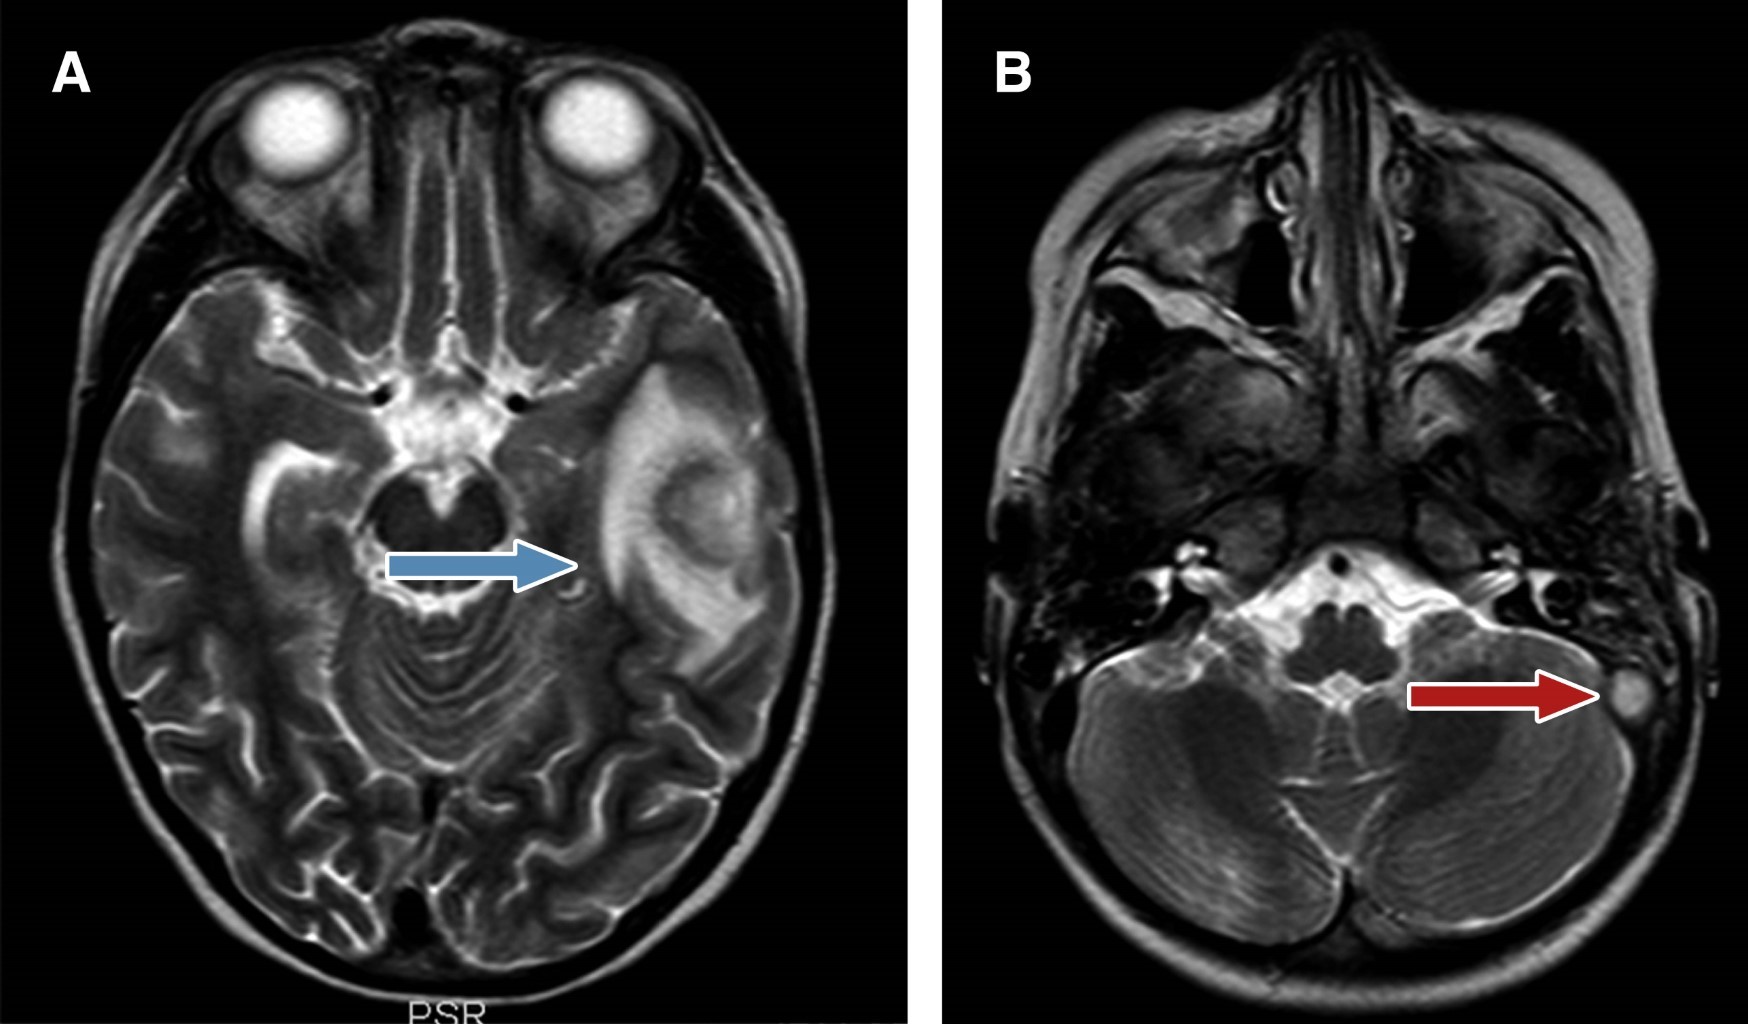

Al examen físico se evidenció otalgia izquierda asociada a dolor y aumento en la sensibilidad en la región mastoidea. Los exámenes solicitados revelaron leucocitosis (18.770/mm3) con neutrofilia, trombocitosis (628.000/mm3), elevación de reactante de fase aguda PCR 8.35 mg/dL (valores normales 0.10-0.30 mg/dL), elevación de ferritina 250.20 ng/dL (valores normales 7-140 ng/dL). Ante la alta sospecha de otomastoiditis, se inició terapia antibiótica intravenosa con ceftriaxona (100 mg/kg/día) y vancomicina (60 mg/kg/día). La paciente fue valorada por los servicios de neurología, neurocirugía e infectología; se solicitó estudio de imágenes y se realizó tomografía contrastada del cerebro, donde se evidenció una imagen hipodensa en el hemisferio izquierdo, compatible con absceso cerebral, además de signos de trombosis del seno sigmoideo izquierdo. En el corte de hueso mastoideo izquierdo se evidenciaron signos de hiperdensidad, confirmándose la otomastoiditis (Figura 1). Debido a ello, se solicitó resonancia magnética de cerebro (Figura 2), así como venografía cerebral (Figura 3), evidenciándose el absceso en el lóbulo temporal izquierdo, rodeado por edema perilesional y ausencia de flujo sanguíneo en el seno venoso transverso y sigmoideo izquierdo.

Figura 2